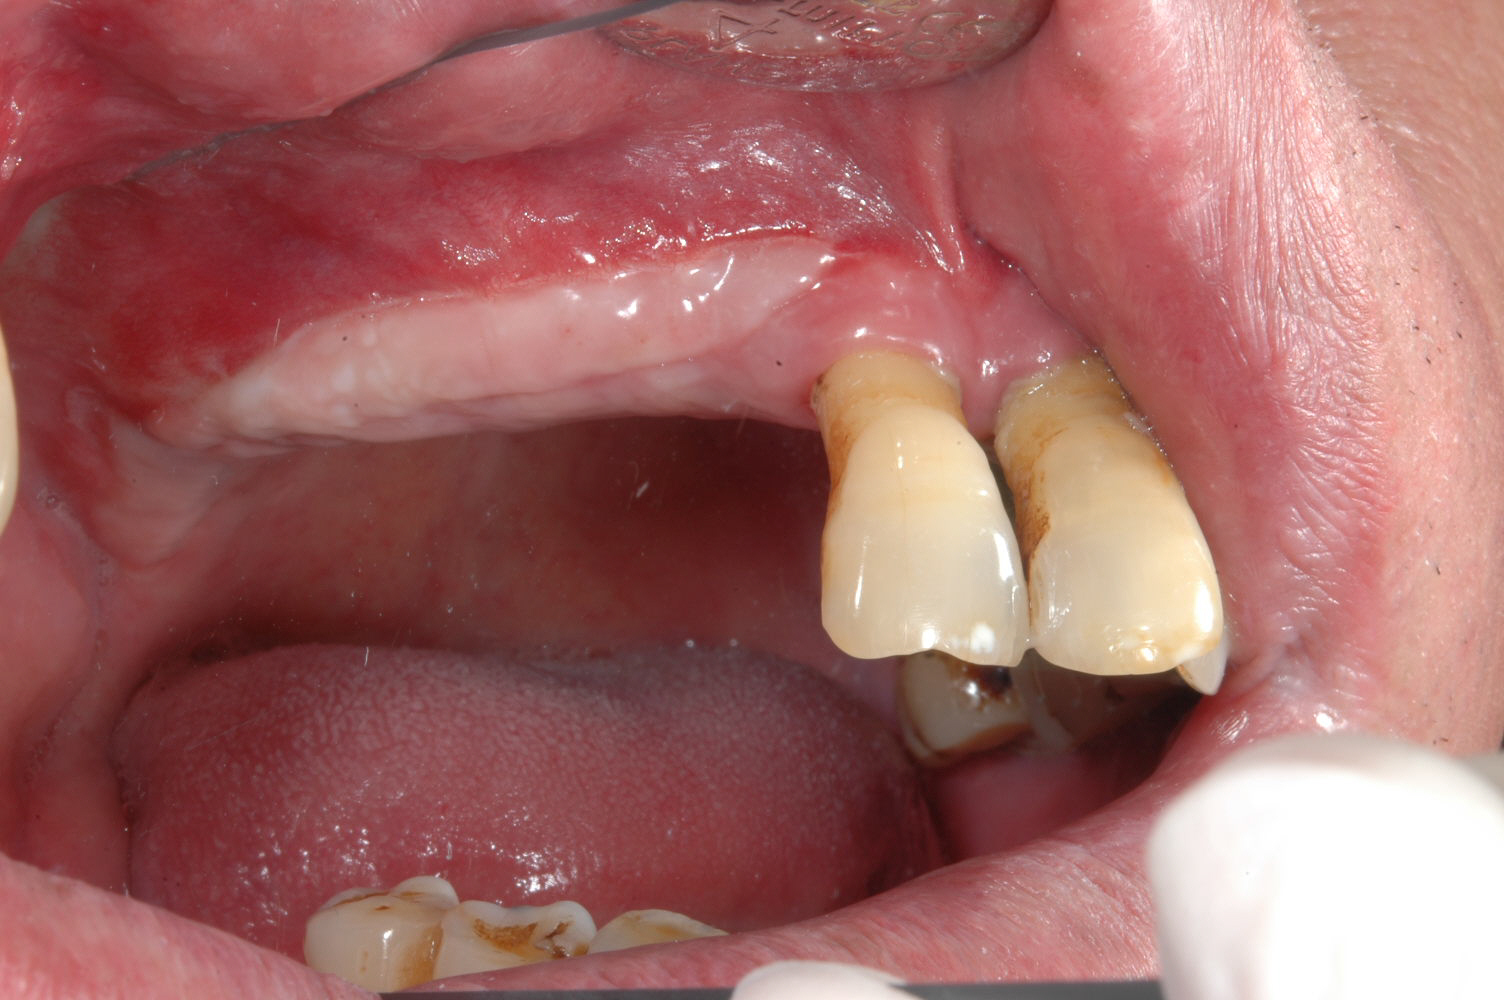

牙齦移植術(補肉)

利用自體牙齦組織移植至牙齦萎縮處或是角質化牙齦不足的地方,恢復牙齦美觀與健康,以利未來植牙提供穩定的牙周環境。